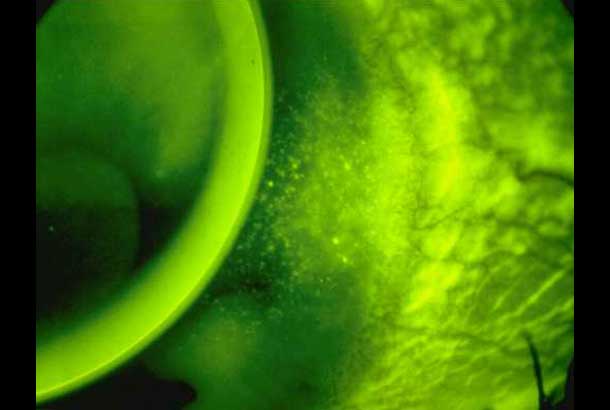

"name": "Dimple Veiling",

"detail": "<p>Staining</p>\n\n<h2>Symptoms</h2>\n\n<ul>\n\t<li>None to mild irritation</li>\n\t<li>May disturb vision if on visual axis</li>\n</ul>\n\n<h2>Signs</h2>\n\n<ul>\n\t<li>Indentations display un-reversed illumination with white light illumination</li>\n\t<li>Multiple, focal areas of sodium fluorescein pooling</li>\n</ul>\n\n<h2>Etiology</h2>\n\n<ul>\n\t<li>Indentations of epithelium resulting from air bubbles (rigid lenses) or mucin balls (soft lenses) trapped under lenses</li>\n\t<li>Most frequently seen with ill-fitting GP lenses (air bubbles) or SiHy lenses (mucin balls)</li>\n\t<li>In GPs, observed centrally with excessive pooling and peripherally with excessive edge lift</li>\n</ul>\n\n<h2>Prevalence</h2>\n\n<ul>\n\t<li>Occasional</li>\n</ul>\n\n<h2>Differential Diagnosis</h2>\n\n<ul>\n\t<li>See: <a href=\"/condition/65\">Epithelial Fluorescein Staining &ndash; Differential</a></li>\n</ul>\n\n<h2>Management</h2>\n\n<ul>\n\t<li>Refit GP lens with closer alignment to corneal shape</li>\n\t<li>Flatter BOZR, smaller TD, change to toric back surface</li>\n\t<li>Lens lubricants with EW SiHy, choose a lens with lower modulus</li>\n</ul>",